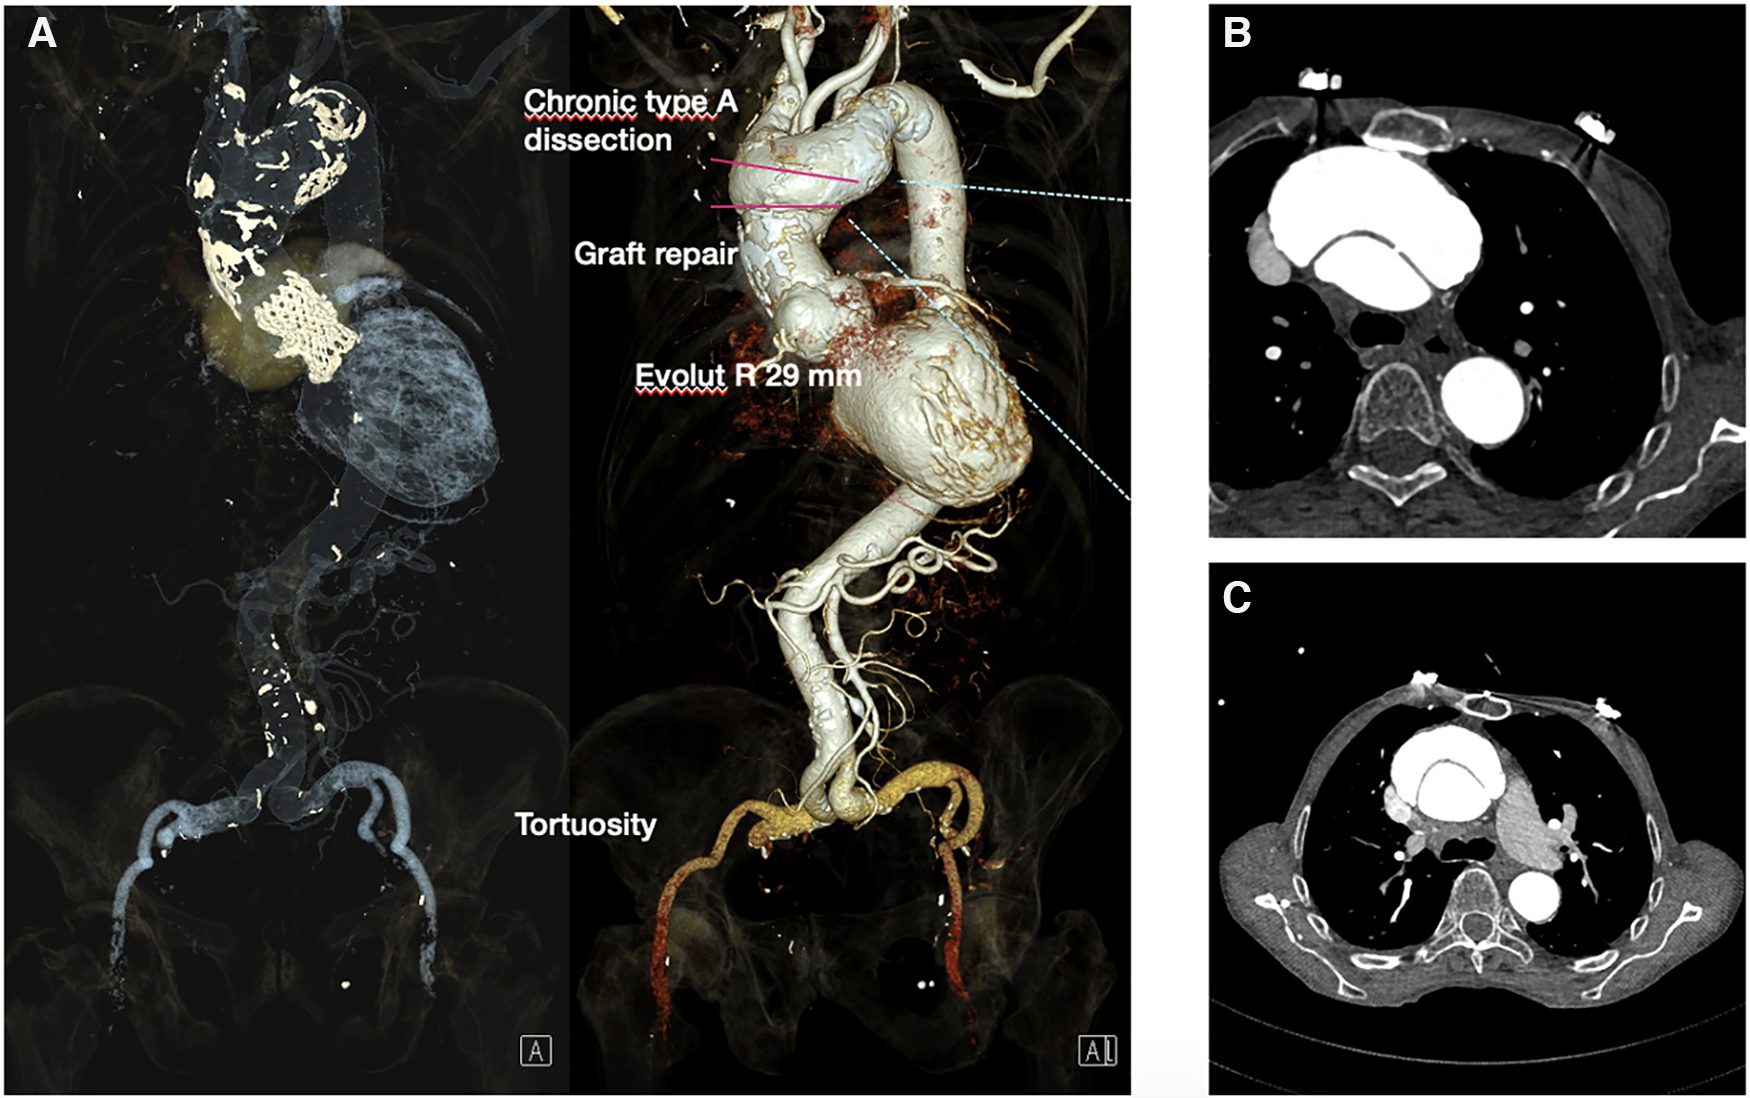

Echocardiography revealed an enlarged left ventricle (EDD 6.4 cm, EDV 305 ml, EDVI 221 ml/m2) with mild wall hypertrophy (IVS 1.1 cm, inf-lat 1.4 cm) with severely reduced ejection fraction, a normal stroke volume (LVEF 22%, SV 70 ml), and severe valvular and paravalvular insufficiency of the Evolut R biological TAVI valve with mild mitral regurgitation. The central valvular insufficiency was caused by the degeneration of the right leaflet, which led to a diagnostic work-up and exclusion of infective endocarditis of the artificial valve—this was ruled out with transesophageal ultrasound (TEE), cardiac magnetic resonance imaging (MRI), and positron emission tomography (PET-CT) scans, in addition to serial blood cultures, which remained sterile. Echocardiographic signs of LV mechanical dyssynchrony were present. These findings were also confirmed by MRI. A CT of the thoracic and abdominal aorta revealed persistence of the ascending aortic aneurysm distal to the graft placement with dissection spanning the ascending aorta and aortic arch and terminating proximal to the aortic isthmus with involvement of the brachiocephalic trunk and progression of the aortic root dilatation compared to previous CT scans (Figure 2, Supplementary Figures S3, S4). Severe tortuosity of the iliac arteries was evident upon 3D reconstruction. Coronary angiography showed no significant atherosclerotic lesions. Infective endocarditis was excluded as the cause of the valve degeneration.

Figure 2

CT angiography following TAVI protocol: (A) EvolutR TAVI valve with graft repair and aortic aneurysm with type A dissection of the ascending aorta and proximal arch. Severe tortousity of the iliac arteries. (B,C) Type A aortic dissection in the transverse plane.